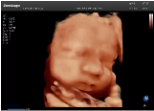

容積探頭是在二維圖像的基礎(chǔ)上,將連續(xù)采集的空間分布位置,經(jīng)過計(jì)算機(jī)重建算法,從而獲得完整的空間形態(tài)。

適用于:胎兒面部、脊柱和肢體等。

優(yōu)勢特點(diǎn):快速獲取、掃查連續(xù)均勻、解剖結(jié)構(gòu)顯示為容積數(shù)據(jù)、準(zhǔn)確進(jìn)行容積測量。